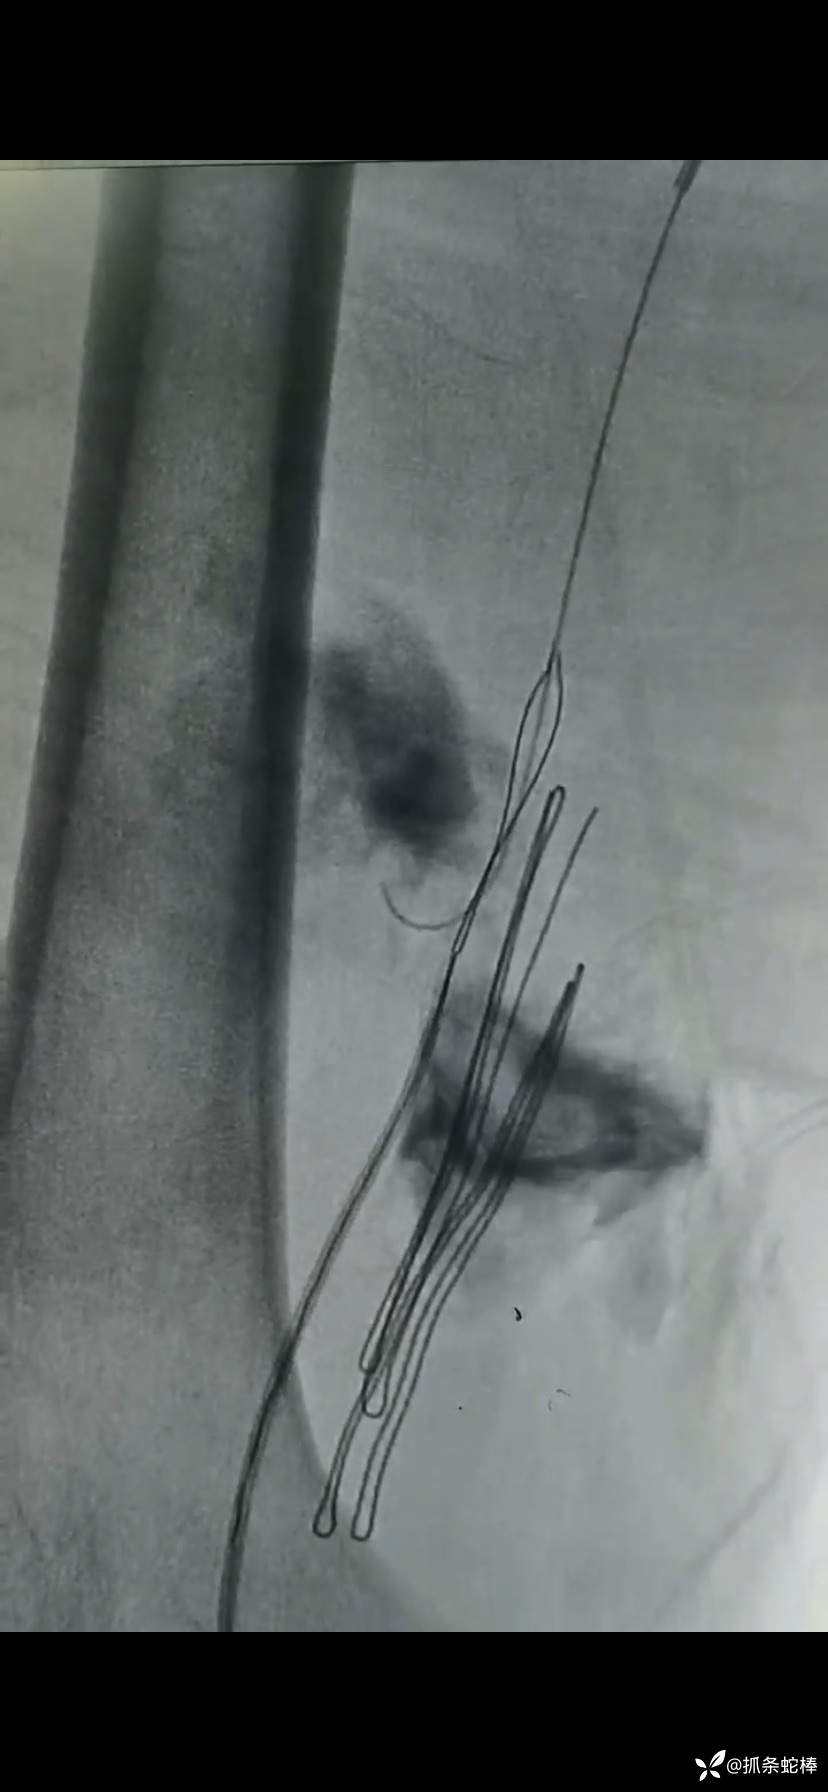

这位创伤后呼吸心跳骤停的患者,随后转入重症监护室进一步的治疗。并且骨科进一步的会诊,打开创口后,缝合处可见喷射状活动性出血。完善彩超检查后怀疑可能有右侧股动脉的损伤。这是检验科回报血红蛋白94g/L,立即为患者申请了输血。

回过头来,继续追问患者的家属,当时到底发生了什么事?他的妻子才支支吾吾的说,和他吵架后,他拿刀子自己捅伤了他的大腿,搞了半天原来是失血性休克导致的呼吸心跳骤,你要是早说,也不至于费这么大的麻烦.由于我院没有血管介入外科,随后将患者转运到上级医院治疗。转运时患者生命体征平稳,有自主肢体动作,镇静插管状态。以下是伤口活动性出血,手术情况。